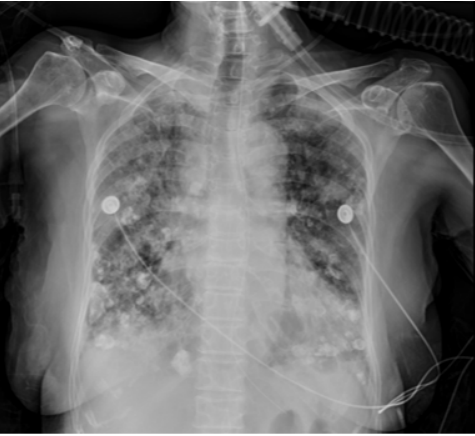

5月4日床边胸片:两肺纹理增多、增粗、模糊,两肺多发斑片模糊影,右侧为著,两肺中下野多发斑片结节状钙化灶;两侧胸腔少量积液可能;心影增大,主动脉迂曲伴壁钙化(图2)

图片

图2  床旁胸片(2023-05-04)

5月12日床旁胸片示患者两肺纹理增多、增粗、模糊,两肺多发斑片模糊影,较5月11日胸片明显进展图5。使用多黏菌素后体温未降,胸片示病变继续进展,激素加量至80 mg q12h。5月12日血气分析提示氧合指数为71 mmHg。与患者及家属沟通后行气管插管有创机械通气(先后予A/C-VC模式、A/C-PC模式、PRVC模式)。5月15日甲泼尼龙加量至160 mg。患者体温变化如图6所示。

图5  患者5月11日和12日胸片变化比较